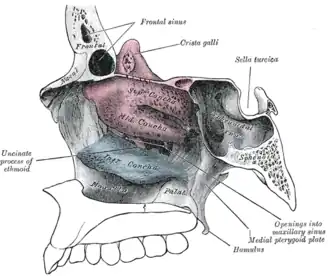

Lateral wall of nasal cavity, showing ethmoid bone in position.

Lateral wall of nasal cavity, showing ethmoid bone in position. -

Roof, floor, and lateral wall of left nasal cavity.

Roof, floor, and lateral wall of left nasal cavity. -